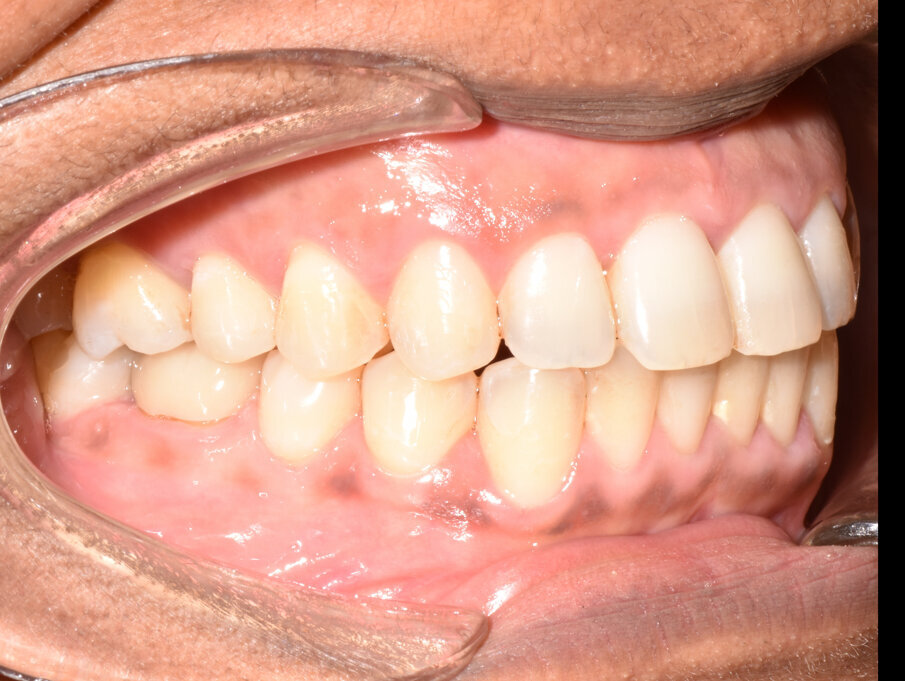

The 31-aligner Spark treatment concluded in five appointments over 7.75 months of active treatment without the need for TADS or refinement aligners. The patient’s excellent compliance was an important factor in the results achieved. Post-treatment photographs demonstrate correction of her Class III, crowded, anterior open bite malocclusion. (Figs. 16-23)

The actual tooth movement closely matched the predicted movement of the digital treatment plan. (Fig. 24) The 31 aligners used with no refinements and the 7.75-month treatment duration are significant.